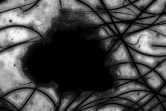

From the fuzzy sets , and three grey probability images are generated , and of in size and a greyscale in . These are defined as follows: , , and

. Evidently, ,

.

These probability images show the pixel probabilities in graphic format, also taking advantage of the fact that as there are three images, a color image can be built by assigning the to the red channel, to the green channel and to the blue channel. This new image is equivalent to the three probability images and enables the result of the fuzzy classification of pixels to be seen much more clearly in graphic format, all of which is shown in Fig. 3.